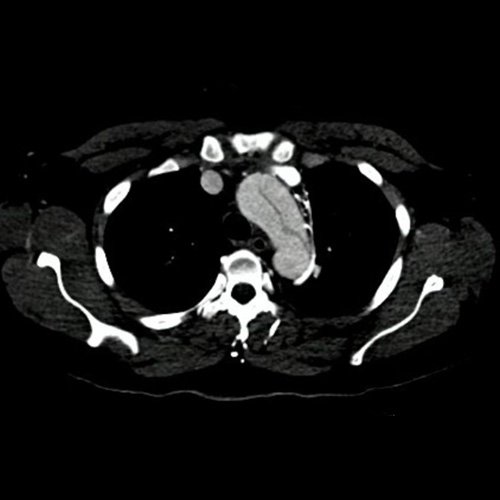

• Angio-TCMS de aorta toracoabdominal y vasos iliofemorales - pre informe (día 0): Interpretación: Se identifica un flap de disección aórtica, que se extiende desde la raíz aórtica, hasta el segmento distal de la aorta torácica descendente, asociado a dilatación aneurismática de la raíz aórtica y la aorta ascendente. No se observa disección de aorta abdominal al momento del examen. El flap de disección compromete la aorta ascendente, el arco aórtico y los tres vasos supraaórticos, extendiéndose hacia el tronco braquiocefálico derecho, con compromiso de la arteria subclavia derecha, así como también de la porción proximal de la arteria carótida primitiva izquierda y de la arteria subclavia izquierda. No impresiona compromiso de la emergencia de las arterias coronarias por esta metodología. Diámetros de la Aorta en sus diferentes porciones:  Senos de Valsalva: 40 mm.  Región media de aorta ascendente: 37 mm. Región media del cayado: 23 mm. Región media de la aorta descendente: 22 mm. A nivel de las cruras diafragmáticas: 19 mm. A nivel del origen del tronco celíaco: 18 mm. A nivel infrarrenal: 14 mm. Previo a su bifurcación iliaca: 13 mm. Hipertrofia del ventrículo izquierdo. Derrame pericárdico de 13 mm de espesor a nivel de cara anterior, de densidad promedio de 30 UH. El esófago es de calibre y trayecto normales. El mediastino está en posición central. No se observan adenomegalias mediastinales, axilares o hiliares. El árbol traqueobronquial no presenta alteraciones. Áreas de aneumatosis bibasal. No se observa derrame pleural. El hígado es de forma, tamaño y situación habituales. Su superficie es lisa, y sus bordes son agudos. El parénquima hepático presenta atenuación heterogénea, con áreas hipodensas difusas, hallazgos que podrían estar en relación con trastorno perfusional. Se observa además edema periportal. La vía biliar intra y extrahepática es de calibre conservado. La vesícula biliar es de forma, tamaño y situación normales, sin imágenes que sugieran la presencia de litiasis. Tener en cuenta que este método puede pasar por alto litiasis colesterínicas. Edema perivesicular. El bazo es de forma, tamaño y situación normales. El eje esplenoportal es de calibre y trayecto conservado, permeable. El páncreas es de características normales. El conducto de Wirsung es de calibre conservado. Las glándulas adrenales son normales. Ambos riñones son de forma, tamaño y situación habituales. Concentran y eliminan normalmente la sustancia de contraste, sin evidencia de alteraciones calicopiélicas ni ureterales. La vena cava inferior y las venas ilíacas primitivas, internas, externas y femorales son de calibre y trayecto conservados, permeables. No se observan adenomegalias intraperitoneales, retroperitoneales, ilíacas ni inguinales. No se observan alteraciones a nivel del tracto gastrointestinal. Vejiga con escasa repleción, con sonda balón en su interior. El útero es de forma, tamaño y situación conservada, sin alteraciones densitométricas, en anteversoflexión. En topografía de ambos anexos se observan colecciones líquidas de aspecto funcional que miden 23 mm a izquierda y 18 mm a derecha. Escasa cantidad de líquido libre en el fondo de saco de Douglas. Espondiloartrosis de la columna dorso-lumbar.

Angiotomografía con contraste endovenoso de cayado aórtico. Corte axial.